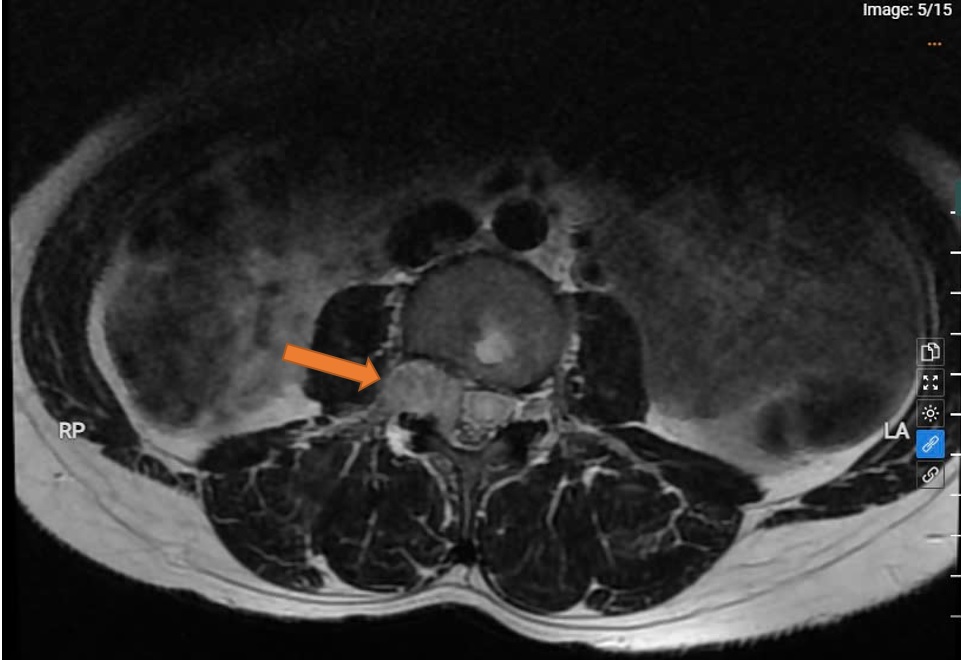

Chị Nguyễn Thị C. nhập viện trong tình trạng tê chân phải kéo dài khoảng 1 tháng, kèm theo cảm giác nặng chân, giảm khả năng vận động. Ban đầu chị nghĩ đến thoát vị đĩa đệm – một bệnh lý phổ biến. Tuy nhiên, qua thăm khám kỹ lưỡng và chụp cộng hưởng từ (MRI), các bác sĩ phát hiện một khối u lớn nằm trong ống sống, đoạn thắt lưng L3-4, đang chèn ép nghiêm trọng lên tủy sống và các dây thần kinh vùng lân cận.

Theo Ths.BS Hoàng Hải Hòa – Trưởng khoa Phẫu thuật Thần kinh Lồng ngực, khối u có kích thước lớn, phát triển âm thầm trong thời gian dài. Nếu không được phẫu thuật kịp thời, bệnh nhân có thể gặp các biến chứng nghiêm trọng như: